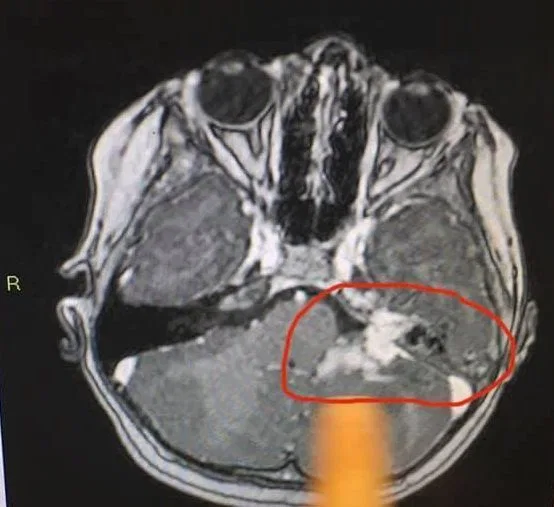

“She spent the night being observed in Wishaw and the CT scan results came the following day and confirmed her diagnosis,” Jemma wrote on Facebook. “She had not one, but THREE puss filled abscesses on her cerebellum which were putting pressure on her optic nerve, hence the squint/dizziness/double vision etc.